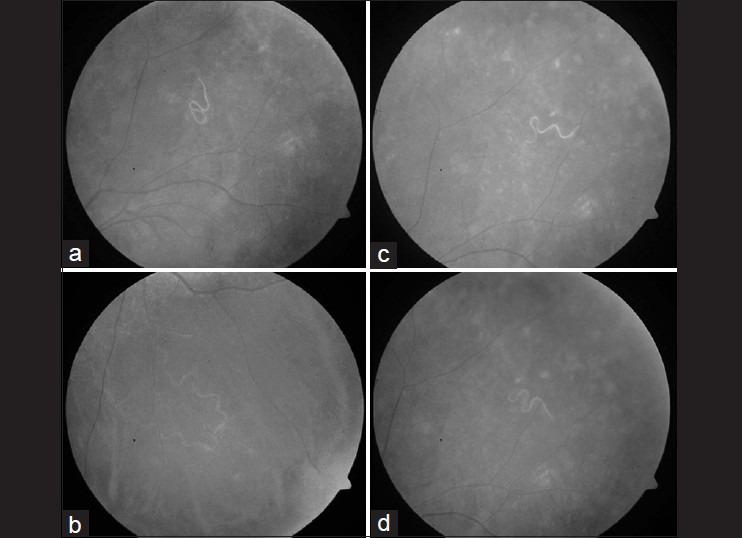

Live subretinal nematode: management by focal argon laser photocoagulation with spectral domain OCT analysis.

Indian J Ophthalmol. 2014 Aug;62(8):899-901. doi: 10.4103/0301-4738.141081.